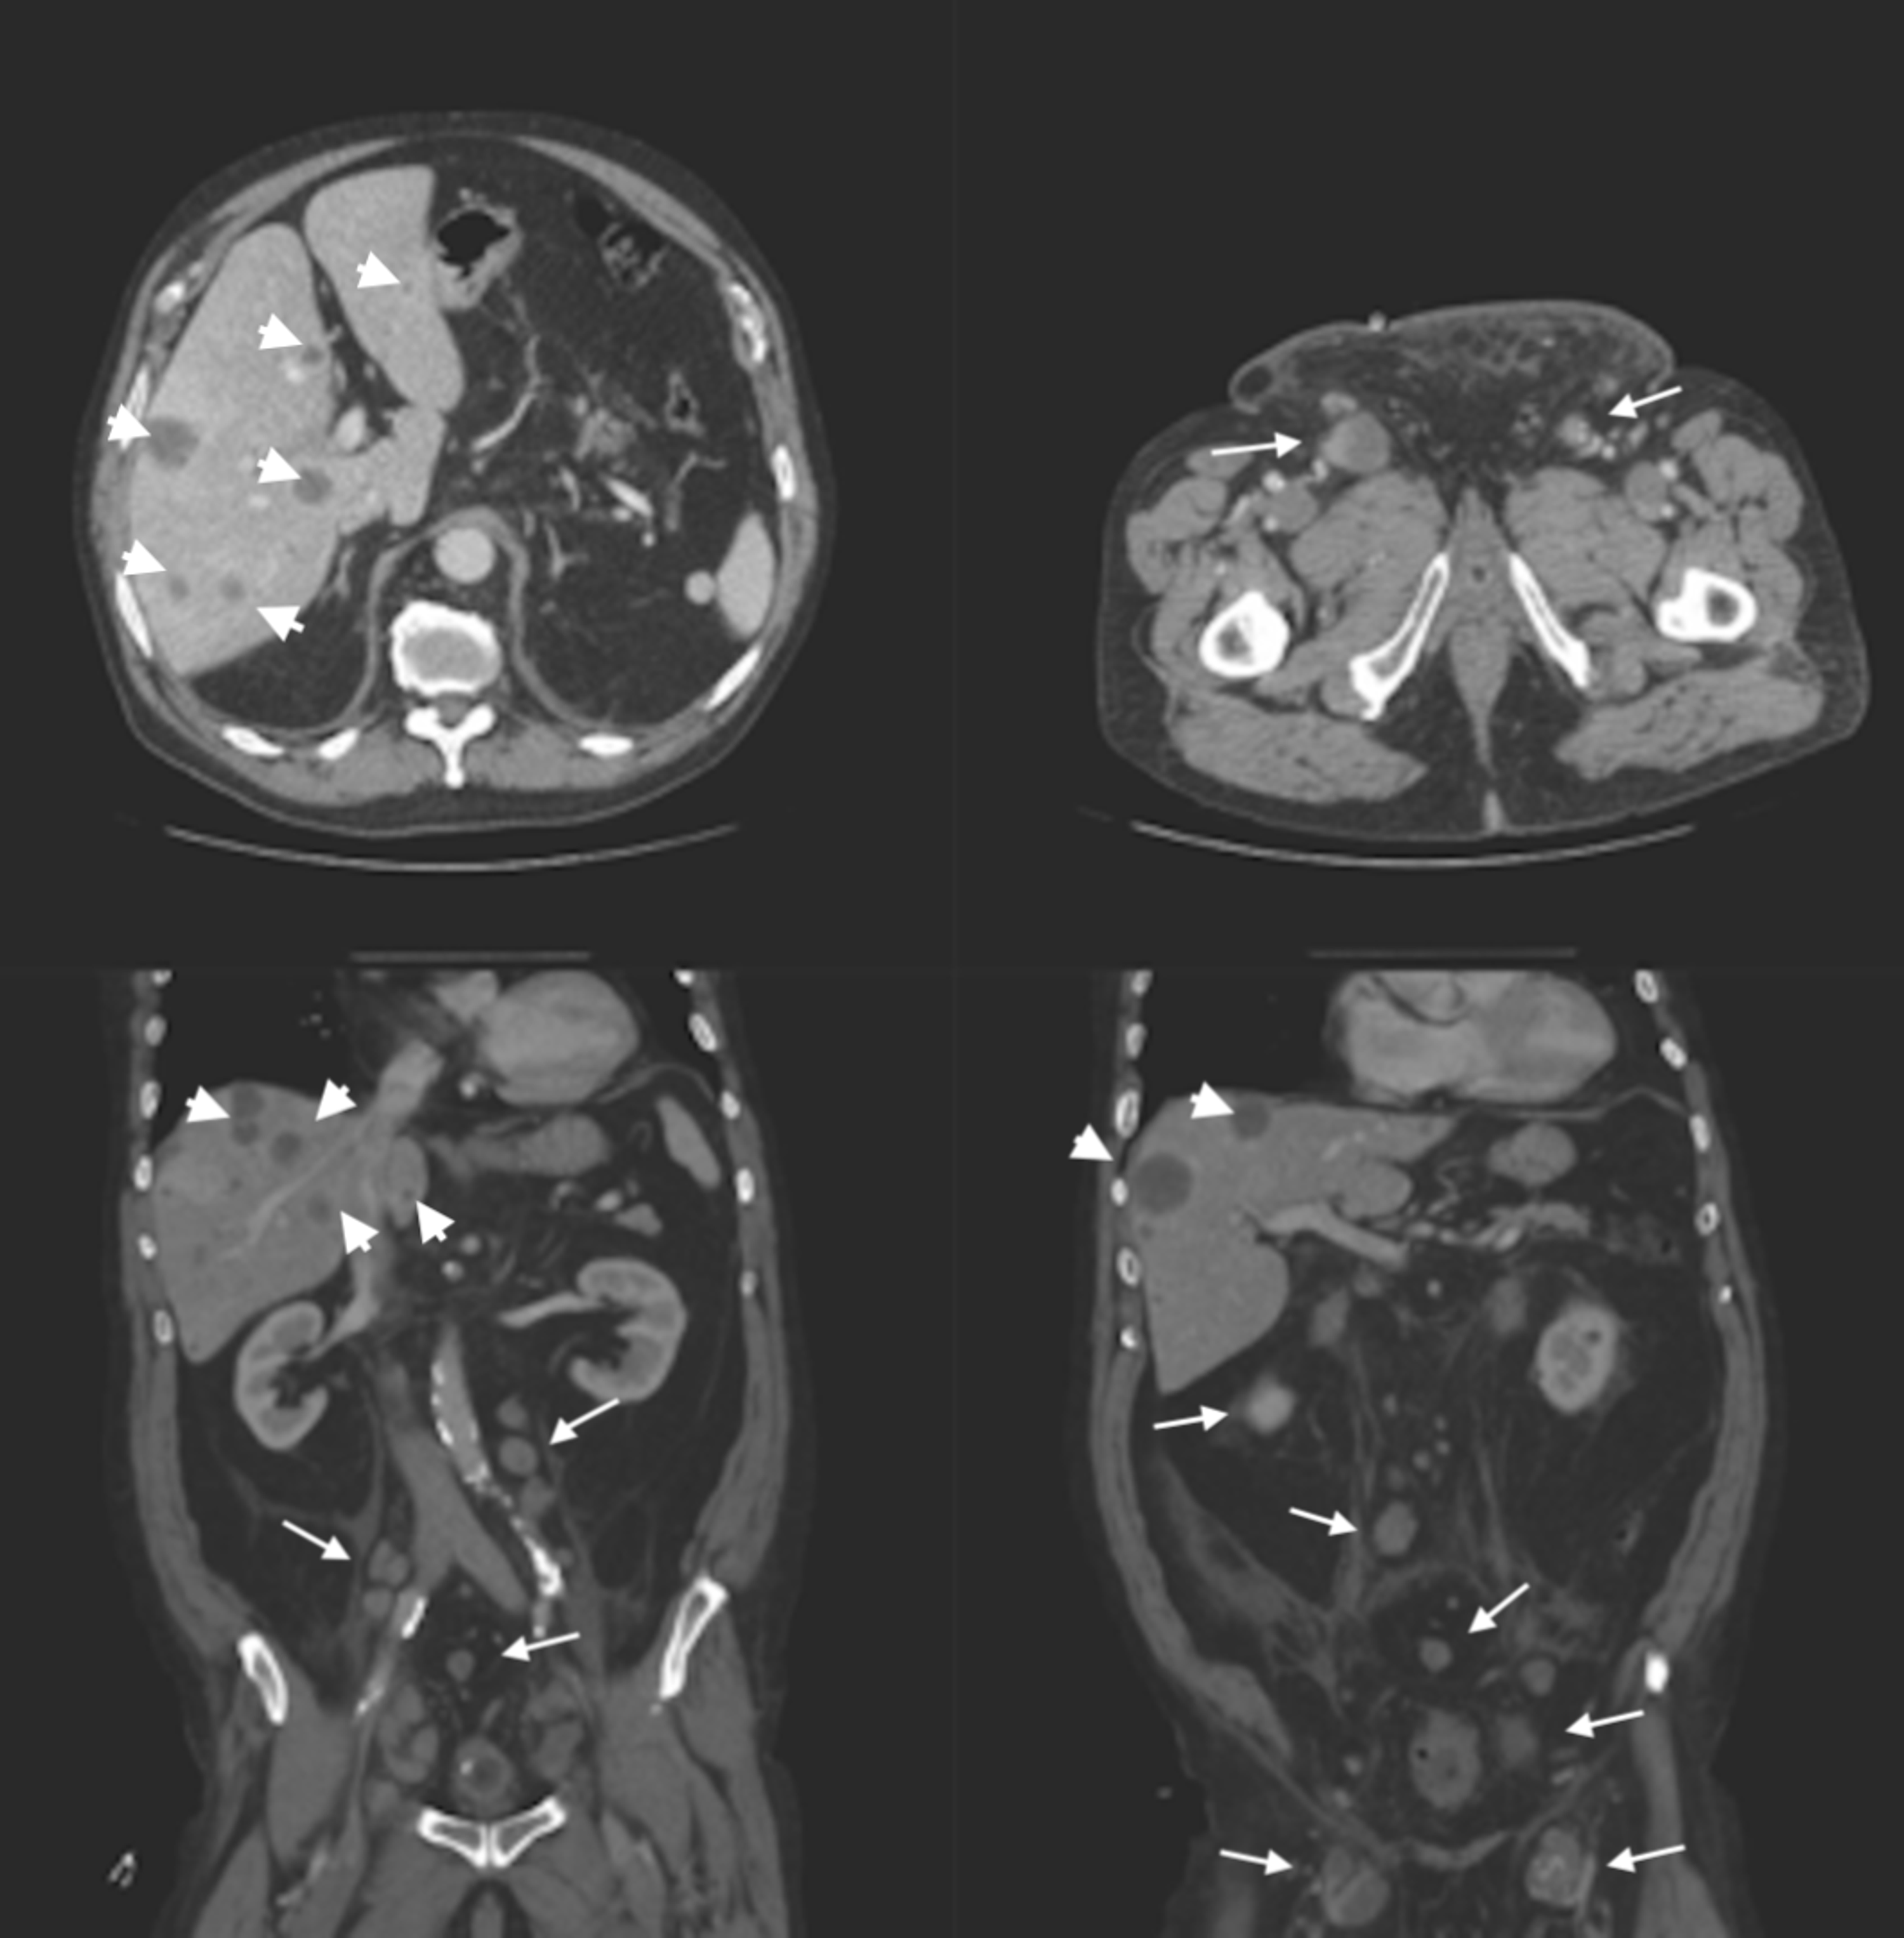

Invasive and noninvasive extramammary perianal Paget's disease

Invasive and noninvasive extramammary perianal Paget's disease Paget's Disease Perianal Perianal paget’s is a rare disease. Perianal paget disease (ppd) is a subset of empd, which arises in the perianal. Extramammary paget’s disease (empd) is a rare type of skin condition that may be associated with different types of cancer. Perianal paget's disease is associated with nonspecific symptoms, frequently delaying diagnosis. Importance extramammary paget disease (empd) is a frequently recurring. Paget's Disease Perianal.